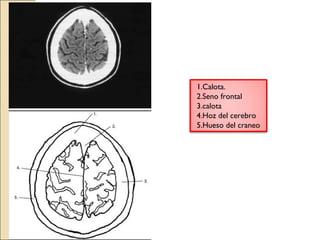

1.Calota.

2.Seno frontal

3.calota

4.Hoz del cerebro

5.Hueso del craneo